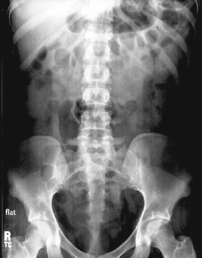

Certain positioning landmarks are essential for positioning the general abdomen and specific organs within the abdomen because the borders of these organs and the upper and lower margins of the general abdomen itself are not visible from the exterior.

Abdominal borders and organ locations, however, can be determined by certain landmarks, which can be located by gentle palpation with the fingertips, being careful of painful or sensitive areas. (The patient should be informed of the purpose for this before beginning the palpation process.)

• Center of IR to level of iliac crests, ensuring that upper margin of symphysis pubis is included on lower IR margin. (A large hypersthenic patient may require that the IR be placed crosswise with a second IR centered higher.)

• Center IR to iliac crest—ensure that bladder area, including the symphysis pubis, is included at lower IR margin.